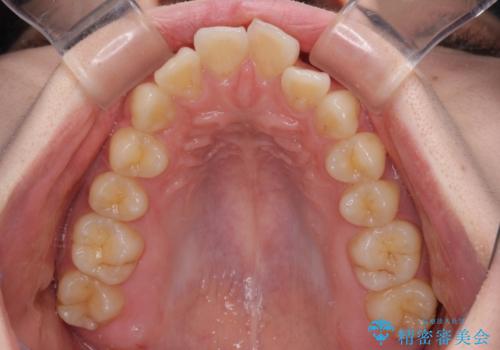

- 下顎の前歯が上顎の歯肉に咬みこむくらいに突出した上顎前歯を気にして来院された患者様です。

口元の突出感はないものの、上顎前歯が前方に傾斜して突出しており、前後に大きなズレがあり非常に深い咬み合わせとなっていました。

前突間を改善するため、上顎左右の第一小臼歯を抜歯してワイヤー装置にて矯正治療を行うこととしました。